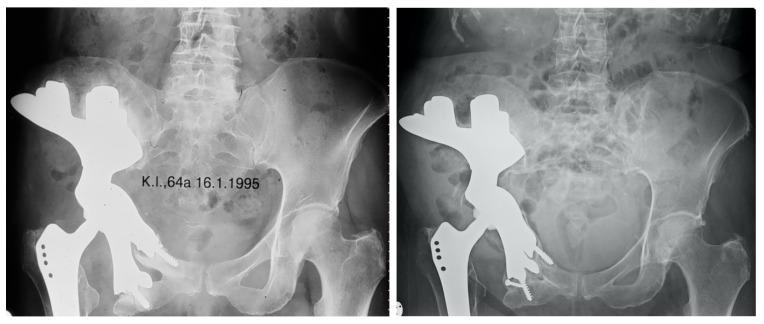

Patient-Specific Implants for Pelvic Tumor Resections.

Introduction Limb salvage surgery for periacetabular malignancies is technically demanding and associated with a considerable likelihood of postoperative complications and surgical revision. Reconstruction using custom-made implants represents the treatment of choice. This study was conducted to analyze treatment outcomes of custom-made implants in a single orthopaedic tumor center. Patients and Methods Twenty patients with a histologically verified periacetabular malignancy and a median follow up time of 5 (1-17) years were included. Results The median number of revision surgeries per patient was 1.5 (0-7). Complications were dislocations in 3 patients, aseptic loosening in 4 patients, deep infections in 9 patients, thromboembolic events in 5 patients and sciatic nerve lesions in 4 patients. Overall survival was 77% after one year, 69% after two years and 46% after five years. Median Harris Hip Score was 81 (37-92) points at last follow up. Conclusion Although internal hemipelvectomy and reconstruction using custom-made implants is linked with a high risk of postoperative complications, good functional outcomes can be regularly achieved. This information may help treating surgeons to find adequate indications, as eligible patients need to be critically selected and integrated into the decision-making process.

引言 髋臼周围恶性肿瘤的保肢手术技术要求高,术后并发症和手术翻修的可能性很大。使用定制植入物进行重建是首选的治疗方法。本研究旨在分析单个骨科肿瘤中心定制植入物的治疗效果。

患者与方法 纳入20例经组织学证实的髋臼周围恶性肿瘤患者,中位随访时间为5(1-17)年。

结果 每位患者的翻修手术中位数为1.5(0-7)次。并发症包括3例脱位、4例无菌性松动、9例深部感染、5例血栓栓塞事件和4例坐骨神经损伤。1年后总生存率为77%,2年后为69%,5年后为46%。末次随访时Harris髋关节评分中位数为81(37-92)分。

结论 尽管半骨盆切除术加定制植入物重建术后并发症风险高,但仍可经常获得良好的功能结果。这些信息可能有助于治疗外科医生找到合适的适应症,因为需要严格挑选合适的患者并将其纳入决策过程。